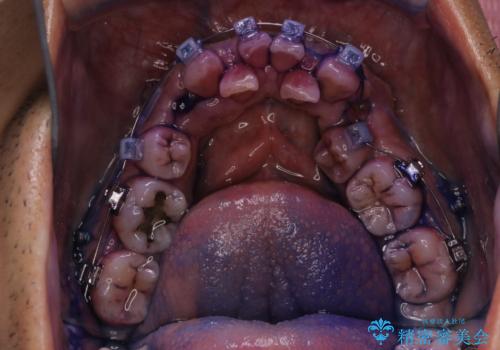

- ワイヤー装置で矯正中の方です。歯磨きがしずらく、専門的な機械でクリーニングしてほしいとの事でした。PMTC60分コースを行いました。

ワイヤー矯正中はブラッシングが難しくなるため、磨き残しが多くなることがあります。適切な道具を使って、適切なブラッシング方法を習得することで、磨き残しを減らすことができます。

また、矯正で歯の移動があると今までなかったところに隙間が出てきたり、ガタつきが解消されてきたりすることで、お口の中の環境が変わります。

矯正治療中も清潔な口腔内を保つことは、とても大切です。そのため、定期的に専門的な機械・材料を使用したProfessinnalcleaning(pmtc)を行うことがおススメです。